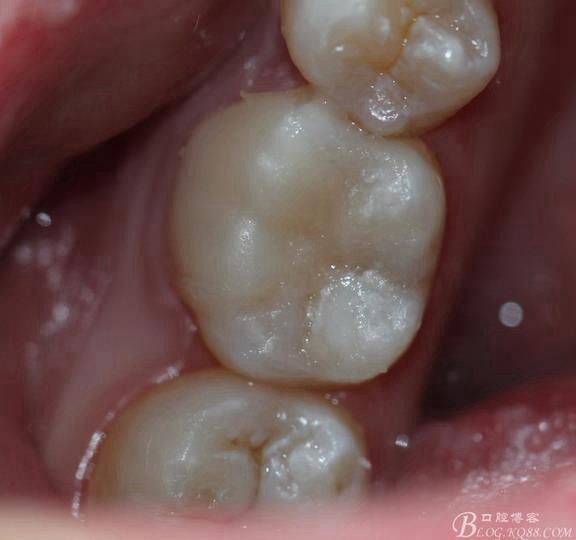

粘接 去除多余的粘結(jié)劑 進行光照 調(diào)HE 一周后進行拋光

復診拋光 很容易看到邊緣線,原因是主要有兩個:一-瓷塊選擇不準確,目前我們單位瓷塊顏色單一。二- 粘結(jié)劑,選擇和牙體顏色不一致的。我選擇的偏白,所以邊緣白線較明顯。

總結(jié):歷時2周時間結(jié)束,比較累。整體感覺沒有想象中那么好,總也做不出樹脂嵌體的那種渾然天成的感覺。